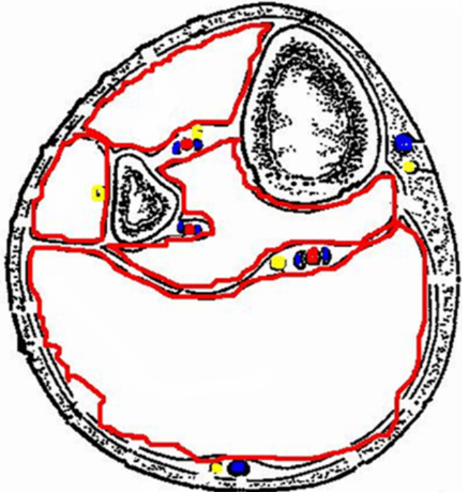

Tryckmätning, se bild. Vad är farligt tryck?

Prover, vilka är viktigast att ta gällande compartment (2)?

A

• Högre än det arteriella tryckets diastole

o Perfusionstryck ska vara 30 iaf men vi har -10

• CK och myoglobin (är iofs högt efter trauma)